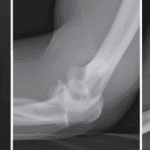

X-rays

are typically ordered to evaluate the underlying bone. They commonly reveal a bone lesion altering the bone’s shape and strength, often appearing enlarged with a clear central space and thin cortex.